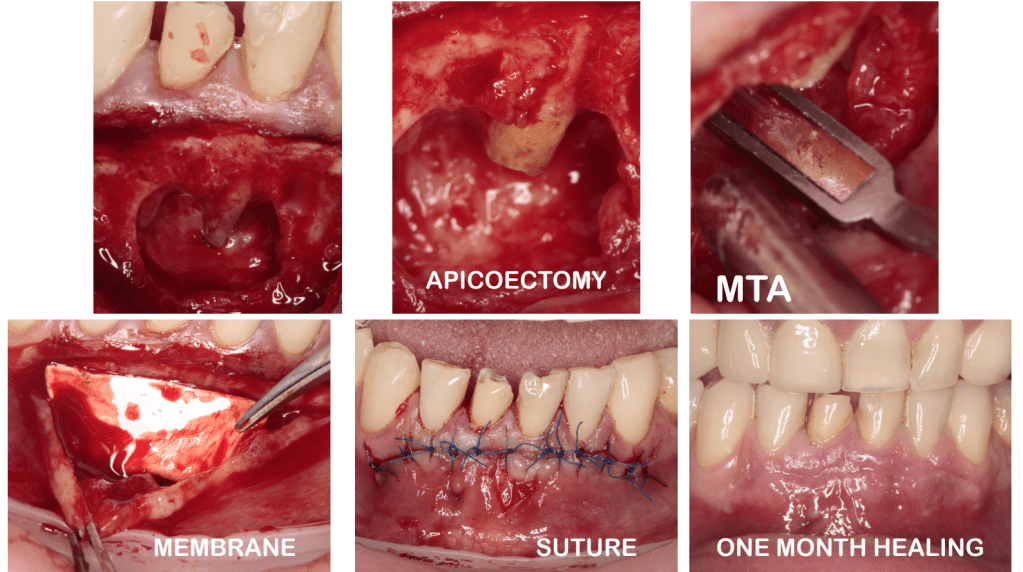

Cirugía apical

Cirugía canino puente